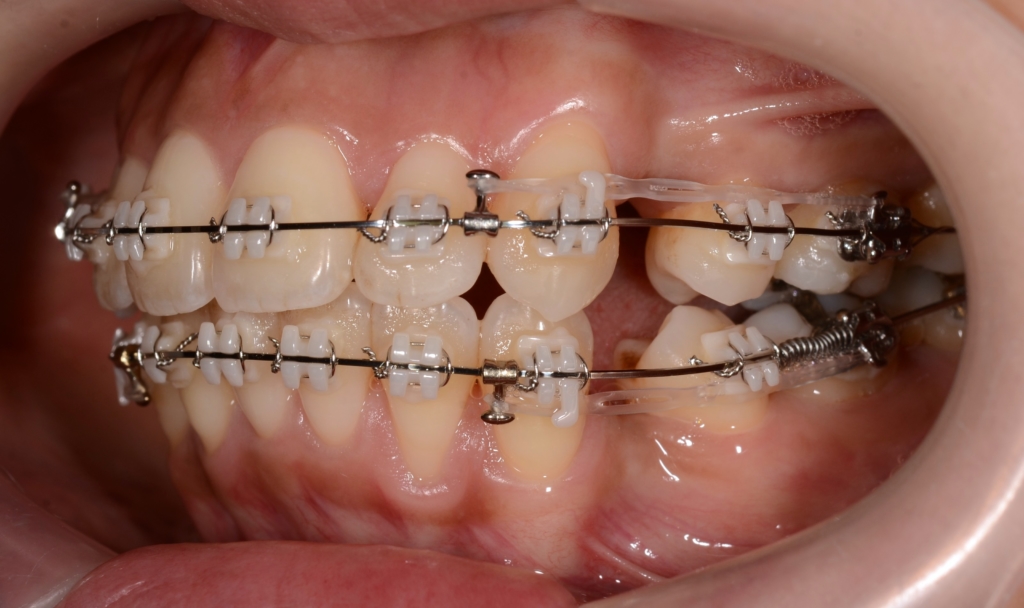

マルチブラケットシステム(スタンダード type)で矯正を開始。

上下とも前歯がきれいに並んだので、噛み合わせを考えながら前歯を引っ込めて隙間を閉鎖します。

【このステップで考えたのは・・・】

今回は、「出来るだけたくさん上の前歯を引っ込めて、下は上の歯並びに合わせる」という治療計画です。

というのも、「口元は引っ込めたいが、アンカースクリューは絶対に嫌!」という強い要望がありました。

奥歯の噛み合わせが上顎前突(いわゆる出っ歯)の噛み合わせなので、普通に前歯を引っ込めて行くと、最後に出っ歯が残ってしまいます。

本来口元を引っ込めることを狙うなら、その時点からアンカースクリューを用いて上の歯列を更に後方へ引っ込めて、口元が最大限に変化するよう頑張ります。

でも、今回は患者さんの要望でアンカースクリューが使えないので、その作戦は出来ません。

そこで、上の前歯は最大限に引っ込めるけれど、下の隙間は前歯と奥歯のお互いが動いて良い感じ(!)で無くなるように!という作戦を立てました。

そのために、2級顎間ゴムというものを、長期に渡り併用しました。

緑色の丸で囲んだ中にある「下の奥歯から上の前歯にかかる矯正用のゴム」が2級顎間ゴムです

結局、約1年8か月の間、顎間ゴムを使い続けて頑張ってもらいました。